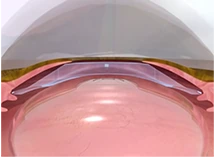

글레이즈는 홍채와 수정체

사이에 반영구적으로 삽입되는

후방안내삽입렌즈로

외관상 보이지 않습니다.

렌즈 삽입 수술 시 2.8mm 최소

절개를 통해 조직 손상과

수술 후 불편함을 최소화하여

빠른 회복이 가능합니다.

렌즈 재질에 자외선

차단제가 함유되어있어

유해한 광선을 차단하고

망막을 보호합니다.